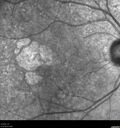

80 year old female Recent vision loss in the left eye for about 6 weeks.

Hyperlipidemia, HTN, Angina, history of TIA’s

ASA daily

VA 20/25 OD, 20/63 OS (was 20/40 5/3/21 at patients first visit)

AC pseudophakic